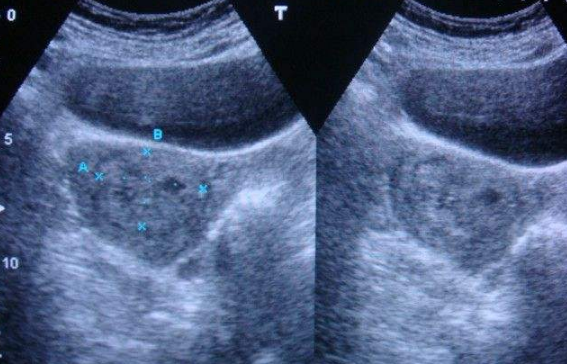

雙角子宮圖片

雙角子宮 (8)